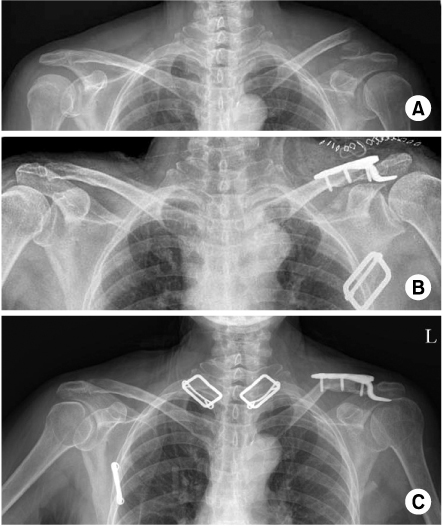

Fig. 1

(A) Preoperative radiograph of the left shoulder of a 55 year old male shows distal clavicle fracture.

(B) This is postoperative radiograph with Hook plate fixation.

(C) At 4 months follow-up, implant is removed without any complication. Bony union is achieved.

Fig. 1 (A) Preoperative radiograph of the left shoulder of a 55 year old male shows distal clavicle fracture. (B) This is postoperative radiograph with Hook plate fixation. (C) At 4 months follow-up, implant is removed without any complication. Bony union is achieved.